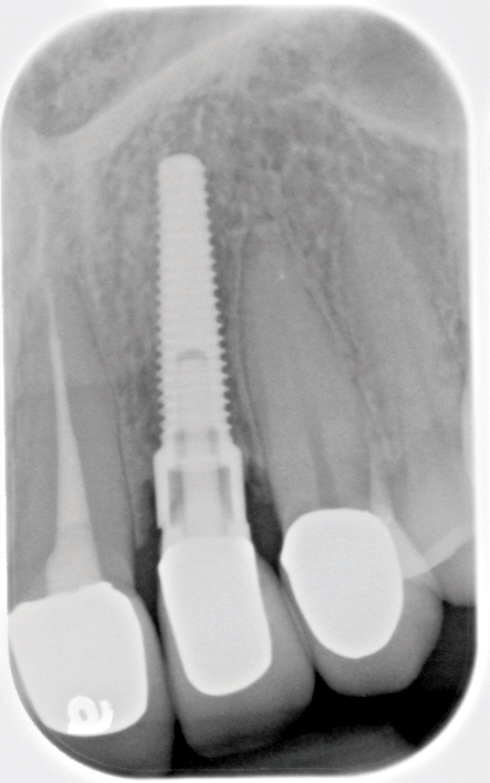

Fig 6. Radiograph following crown fracture.

Figure 6

Fig 9. Radiograph depicting fractured screw inside of the implant.

Figure 9